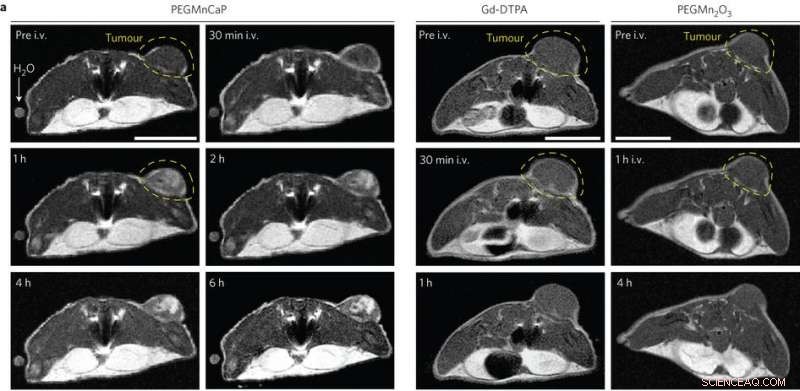

In vivo MR images of subcutaneous C26 tumour-bearing mice pre- and post-intravenous injection (i.v.) of PEGMnCaP (left), Gd-DTPA (centre) and PEGMn2O3 (right) measured with 1 T MRI. Only PEGMnCaP showed a selective and high enhancement of tumour contrast. Scale bar, 1 cm. Credit: (c) Peng Mi et al, Nature Nanotechnology (2016). DOI: 10.1038/nnano.2016.72

These results were promising, so Peng Mi, et al. then tested whether the CaPMnPEG contrast agent worked in solid tumors. Because Mn2+ remains confined within the nanoparticle matrix at physiological pH, CaPMnPEG demonstrate a much lower toxicity compared to MnCl2. MRI studies showed a tumor-to-normal contrast of 131% after 30 minute, which is much higher than Gd-DTPA, a clinically approved contrast agent. After an hour, the tumor-to-normal ratio was 160% and remained around 170% for several hours.